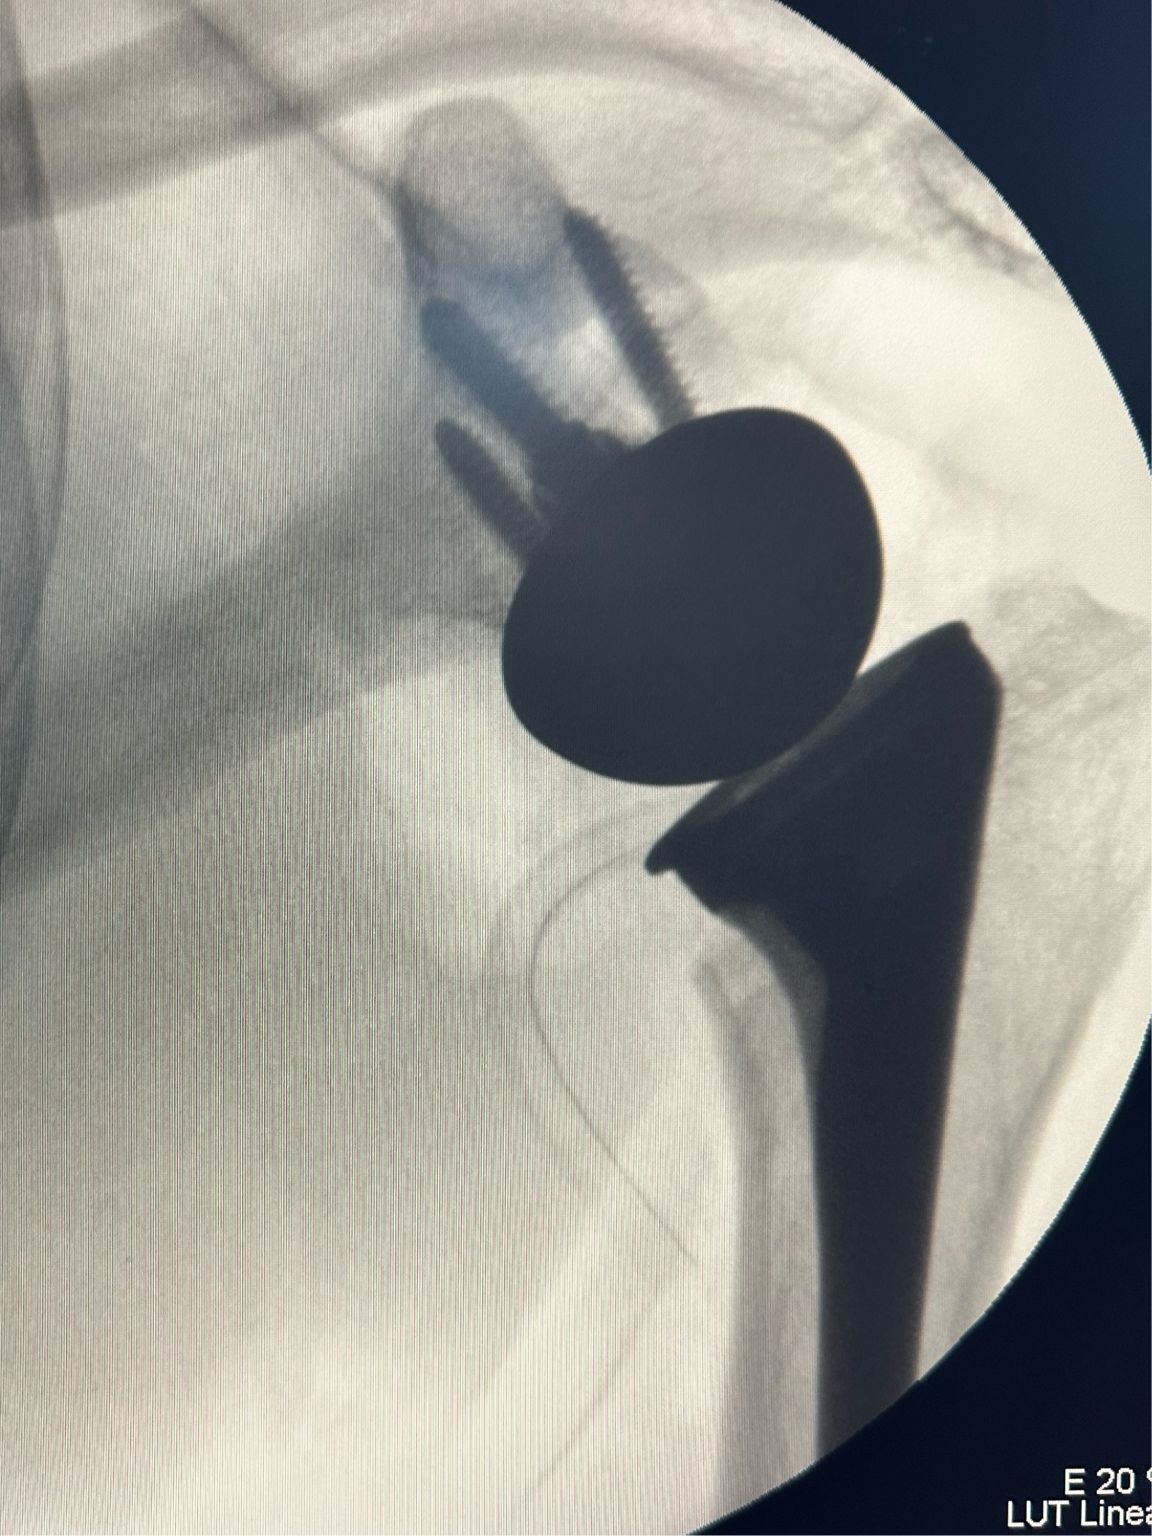

Reverse Shoulder Replacement

Had discussions on Arthroscopic Transosseous Repair, Reverse Shoulder Replacement, and Lower Trapezius Transfers. Explained our protocols and shared experiences. Had an engaging three days in our unit.

#Reverse Shoulder Replacement